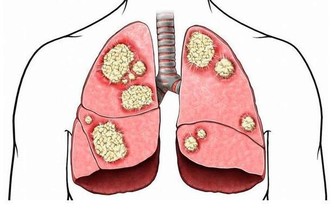

肺癌是中國發病率最高的癌症,也是死亡率最高的癌症。不管是何種癌症,我們都知道,一般發現時都是晚期,很難治愈。如果癌症早期能夠及時發現,經過治療後的五年生存率會大大提升。對於患者來說疾病的早發現要比“靈丹妙藥”見效好!

在德克薩斯州旅行結束後,Bill決定要仔細檢查一下自己的肺,畢竟他是一位有著55年菸齡的老煙民。在找到梅奧診所健康系統肺科的Adel Zurob醫生,醫生了解情況後建議Bill做一項肺癌篩查(低劑量CT)。檢查結果顯示:右肺有一個小的癌變結節。通過進一步的正電子發射斷層掃描(PEC-CT),顯示肺部以外沒有擴散或轉移的徵象。醫生建議,立即進行手術治療。

在醫生切除了Bill的癌變病灶後,還為他進行了胸部檢查以確定是否有淋巴結轉移的跡象,並對可疑的淋巴結進行了預防性切除。Zurob醫生說:“Bill的肺癌治癒的可能性極高,對Bill來講,沒有出現任何轉移是再好不過的了。”